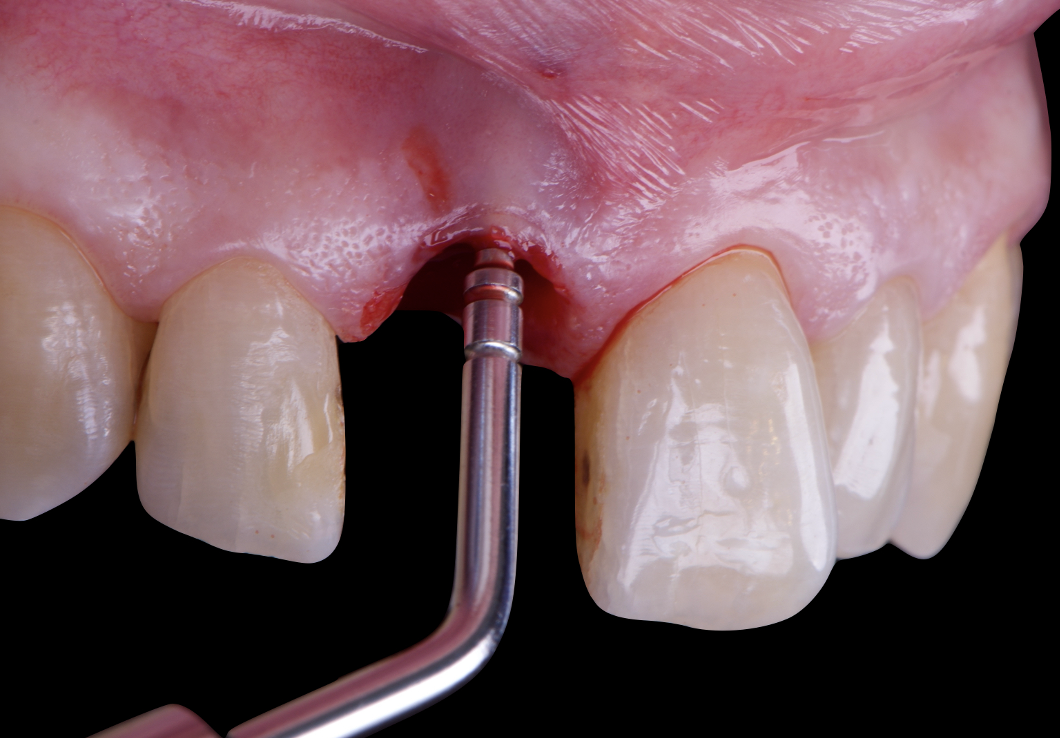

On the same day as the surgery, an immediate-load provisional crown was delivered. This restoration was fabricated in acrylic resin and screw-retained on the implant, following the “one abutment one time” principle. The provisional crown was carefully adjusted to avoid occlusal loading while supporting the peri-implant soft tissue architecture during the healing phase.

The provisional not only satisfied the patient’s functional and esthetic demands but also played a key role in shaping the emergence profile and conditioning the gingival margin. By providing a provisional solution immediately, the patient was able to leave the clinic with a natural-looking smile, avoiding any psychological or social impact associated with tooth loss in the anterior maxilla.

After an appropriate healing period, the definitive prosthesis was planned and delivered. A screw-retained zirconia crown was fabricated to ensure long-term durability, optimal esthetics, and retrievability. Zirconia was selected for its mechanical strength and excellent esthetic properties, blending seamlessly with the adjacent natural dentition in both form and color.